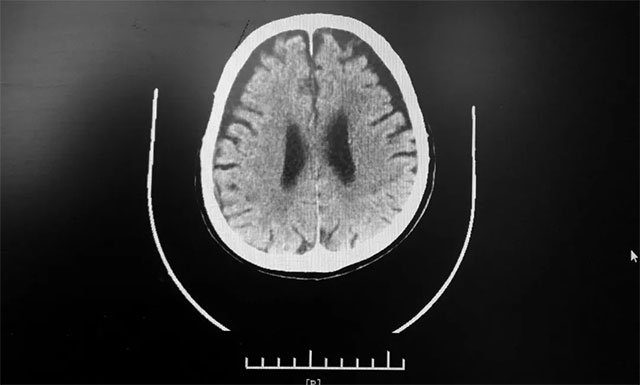

15:00 患者頭部CT檢查完成,影像科3分鐘出報(bào)告,CT報(bào)告排除患者腦出血。根據(jù)影像學(xué)檢查結(jié)果,并結(jié)合其有腦梗發(fā)病史,張琪主任判斷患者為急性腦梗,發(fā)病時(shí)間為12:10分左右,還處于靜脈溶栓治療4.5小時(shí)的時(shí)間窗內(nèi),有溶栓治療指征,可溶栓治療,積極治療血管有再通希望。

▲ 根據(jù)急診CT影像結(jié)果,排除患者腦出血